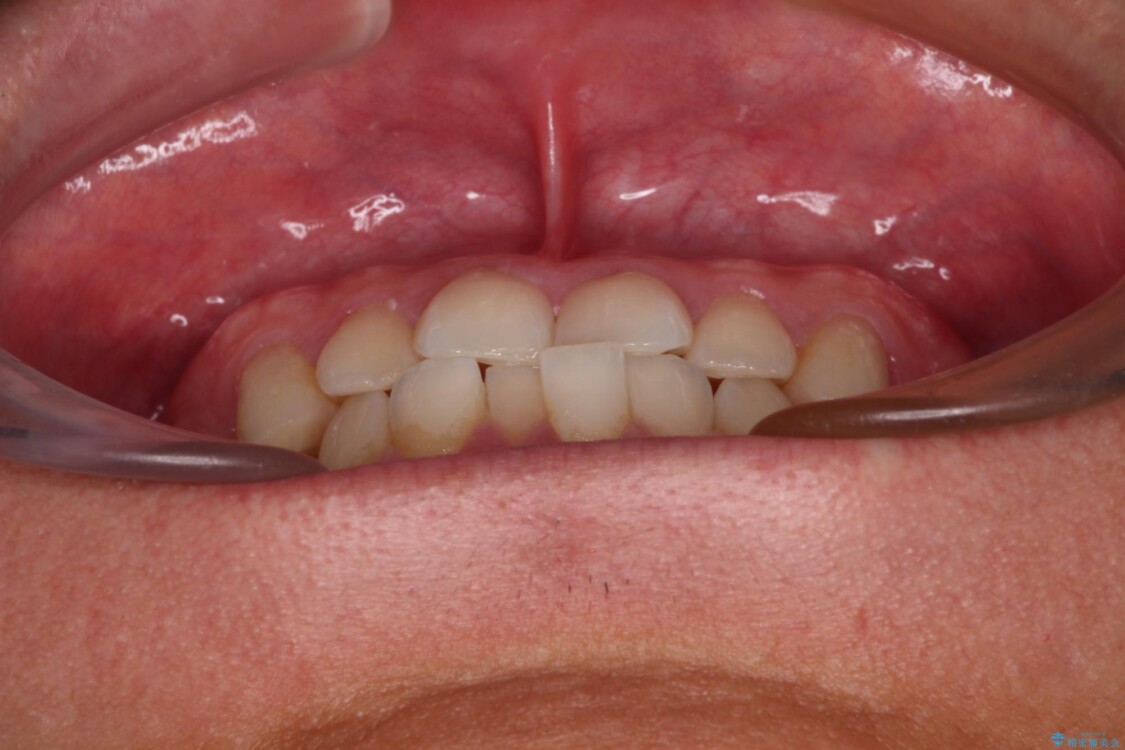

主訴:前歯のデコボコと奥歯のかみ合わせを治したい 今回ご紹介するのは、「前歯のガタガタ(叢生)」と「奥歯のかみ合わせ(シザーズバイト)」にお悩みでご来院された患者様の症例です。 患者様は、 ・歯並びをできるだけ早く改善したい ・費用を抑えた矯正治療 というご要望をお持ちでした。

・上顎左右の第二大臼歯が頬側へ転移し、シザーズバイト(scissors bite)の状態

・上顎左側第二小臼歯が90度捻転しており、噛み合わせに影響

治療前

• 前歯のガタガタ・奥歯のかみ合わせ(シザーズバイト)を改善|1年半で完了したメタルブラケット矯正 治療前画像